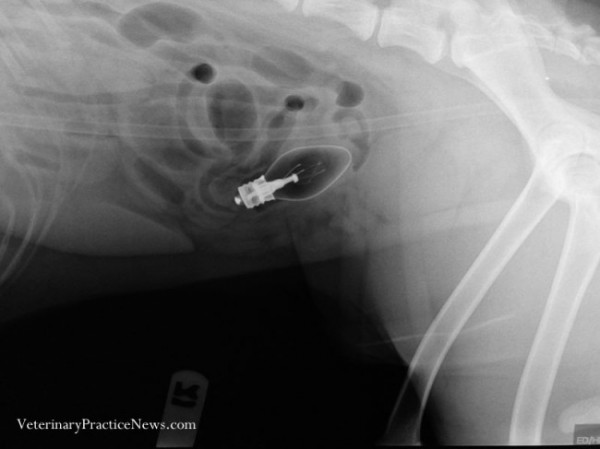

Игрушечная гоночная машинка